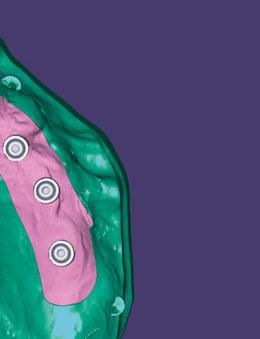

Figuras 12-17.

(USS), como se aprecia en las figuras 23 a 25, comienza la segunda fase de tratamiento. Esta duró tan solo 12 meses debido a que gran parte de las relaciones oclusales habían mejorado durante la etapa anterior. Los resultados finales del tratamiento se observan en las figuras 26 a 30 , con la corrección de la clase molar y canina, el resalte y la sobremordida, el centrado de las líneas 1/2 y la curva de Spee. La mejoría en la macro, mini y microestética facial se aprecia en las figuras 31 a 33 , a pesar de la evidente desviación del mentón hacia

la derecha debida a la asimetría ósea detectada al inicio del tratamiento. En la figura 34 se muestran los cambios producidos por el tratamiento ortopédico-ortodóncico realizado, con la mejoría de casi todos los valores cefalométricos analizados, así como los ángulos de la convexidad (160 º), nasolabial (100 º) y mentolabial (118 º) más cercanos a la norma.